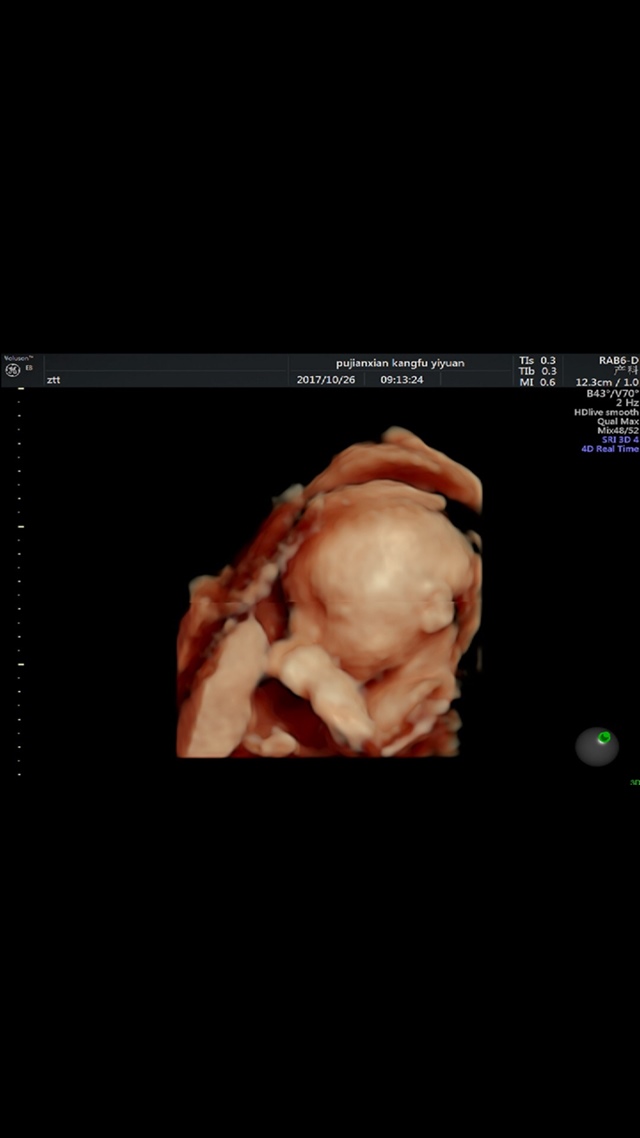

宝宝7个月3天

打隔

孕8周+4天

打嗝